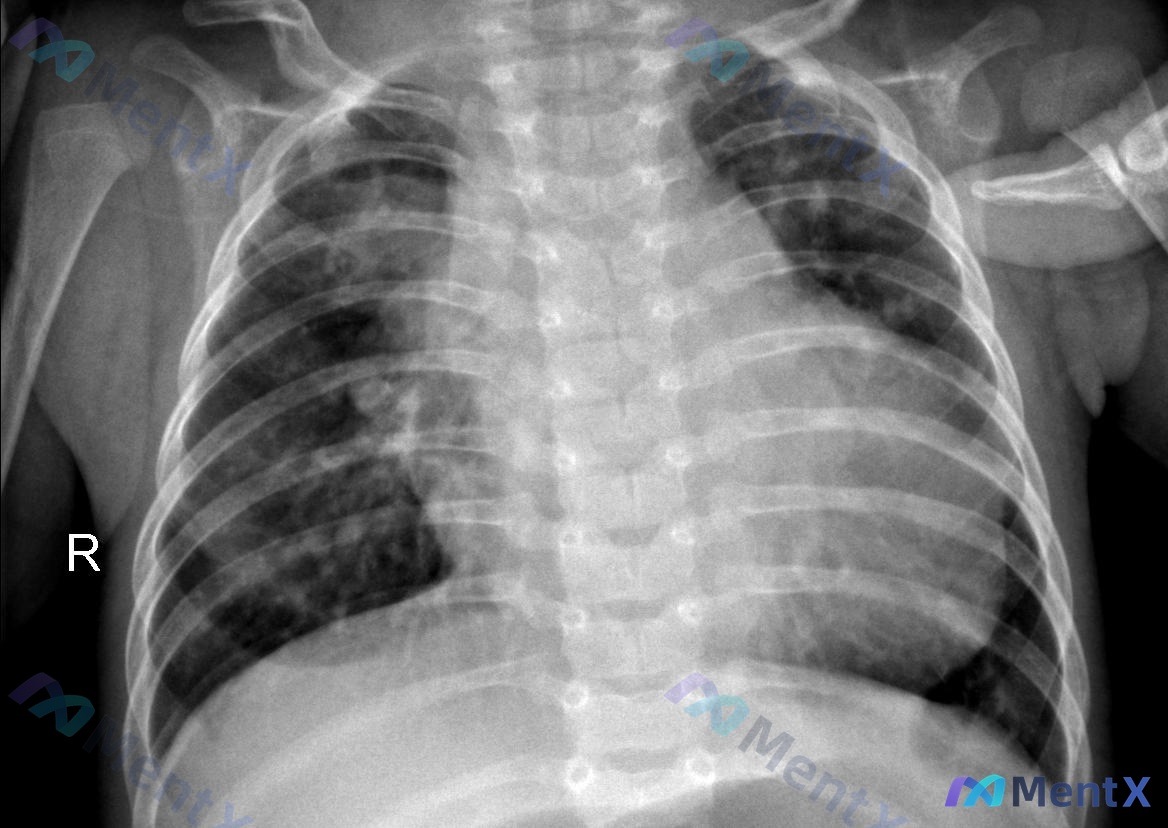

整理了一份婴幼儿的胸部X光影像资料,先把核心信息放出来,大家第一眼会怎么考虑? 基础情况 - 人群:婴幼儿 - 影像类型:胸部正位X光(AP位) 影像关键发现 1. 技术条件: - AP位投照,体位有轻微旋转,吸气深度欠佳(第9-10后肋不可见) - 双侧锁骨上方可见电极片伪影,未遮挡重要肺野 2....

整理了一张儿科胸部X光正位片的资料,先放影像相关的核心表现,大家第一眼会怎么考虑? 基本信息:婴幼儿 投照方式:仰卧位/半卧位 影像核心表现: 1. 双侧肺野可见斑片状及条索状模糊影,以双肺门周围及中内带分布为主,肺纹理走行紊乱、增粗 2. 纵隔上部影增宽,呈典型“帆影”表现 3. 气管居中,肋膈角...

整理到一份儿科胸部正位X光片资料,先纯看影像讨论一下,后面可以再补临床信息。 影像基本情况: - 儿科AP位(前后位)床旁片,吸气、对称、曝光度基本可 - 气管居中,胸廓骨骼、心影、膈肌/肋膈角未见明显异常 - 核心表现:双肺纹理明显增多增粗、走行紊乱;双肺野透亮度欠均匀,可见多发斑片状、云絮状影,...

整理了一份婴幼儿胸部X光的讨论资料,先放核心影像表现: - 仰卧位投照,双肺纹理增多、增粗,走行紊乱 - 双肺野(尤其是肺门周围及中内带)可见弥漫性、散在斑点状及斑片状影,边缘模糊 - 气管居中,心影形态正常,心胸比未见明显异常 - 双侧肋膈角清晰,膈面光滑,未见气胸/胸腔积液 第一眼很多人可能会直...

整理到一份儿科胸部正位X光片的资料,先给大家放核心影像表现: 📋 基本情况:儿科仰卧位前后位(AP)投照 📷 影像核心所见: - 双肺野透亮度欠佳,肺纹理增粗、增强、模糊,呈网格状及小点片状影 - 病变以肺门周围及内中带更明显,双肺门影似乎有增大模糊趋势 - 气管居中,心影形态大致正常,心胸比正常...

整理了一张儿科胸部X光正位片的资料,第一眼很容易往一个方向走,但再仔细看报告里的几个细节,好像思路不能这么快收住。 📋 先放核心影像表现: - 投照条件:仰卧位/半卧位(儿科常用),吸气相一般,膈肌略高 - 肺野:双肺纹理明显增粗、模糊,弥漫分布;双肺门周围及中下肺野透亮度下降,有斑片状模糊影,边界...